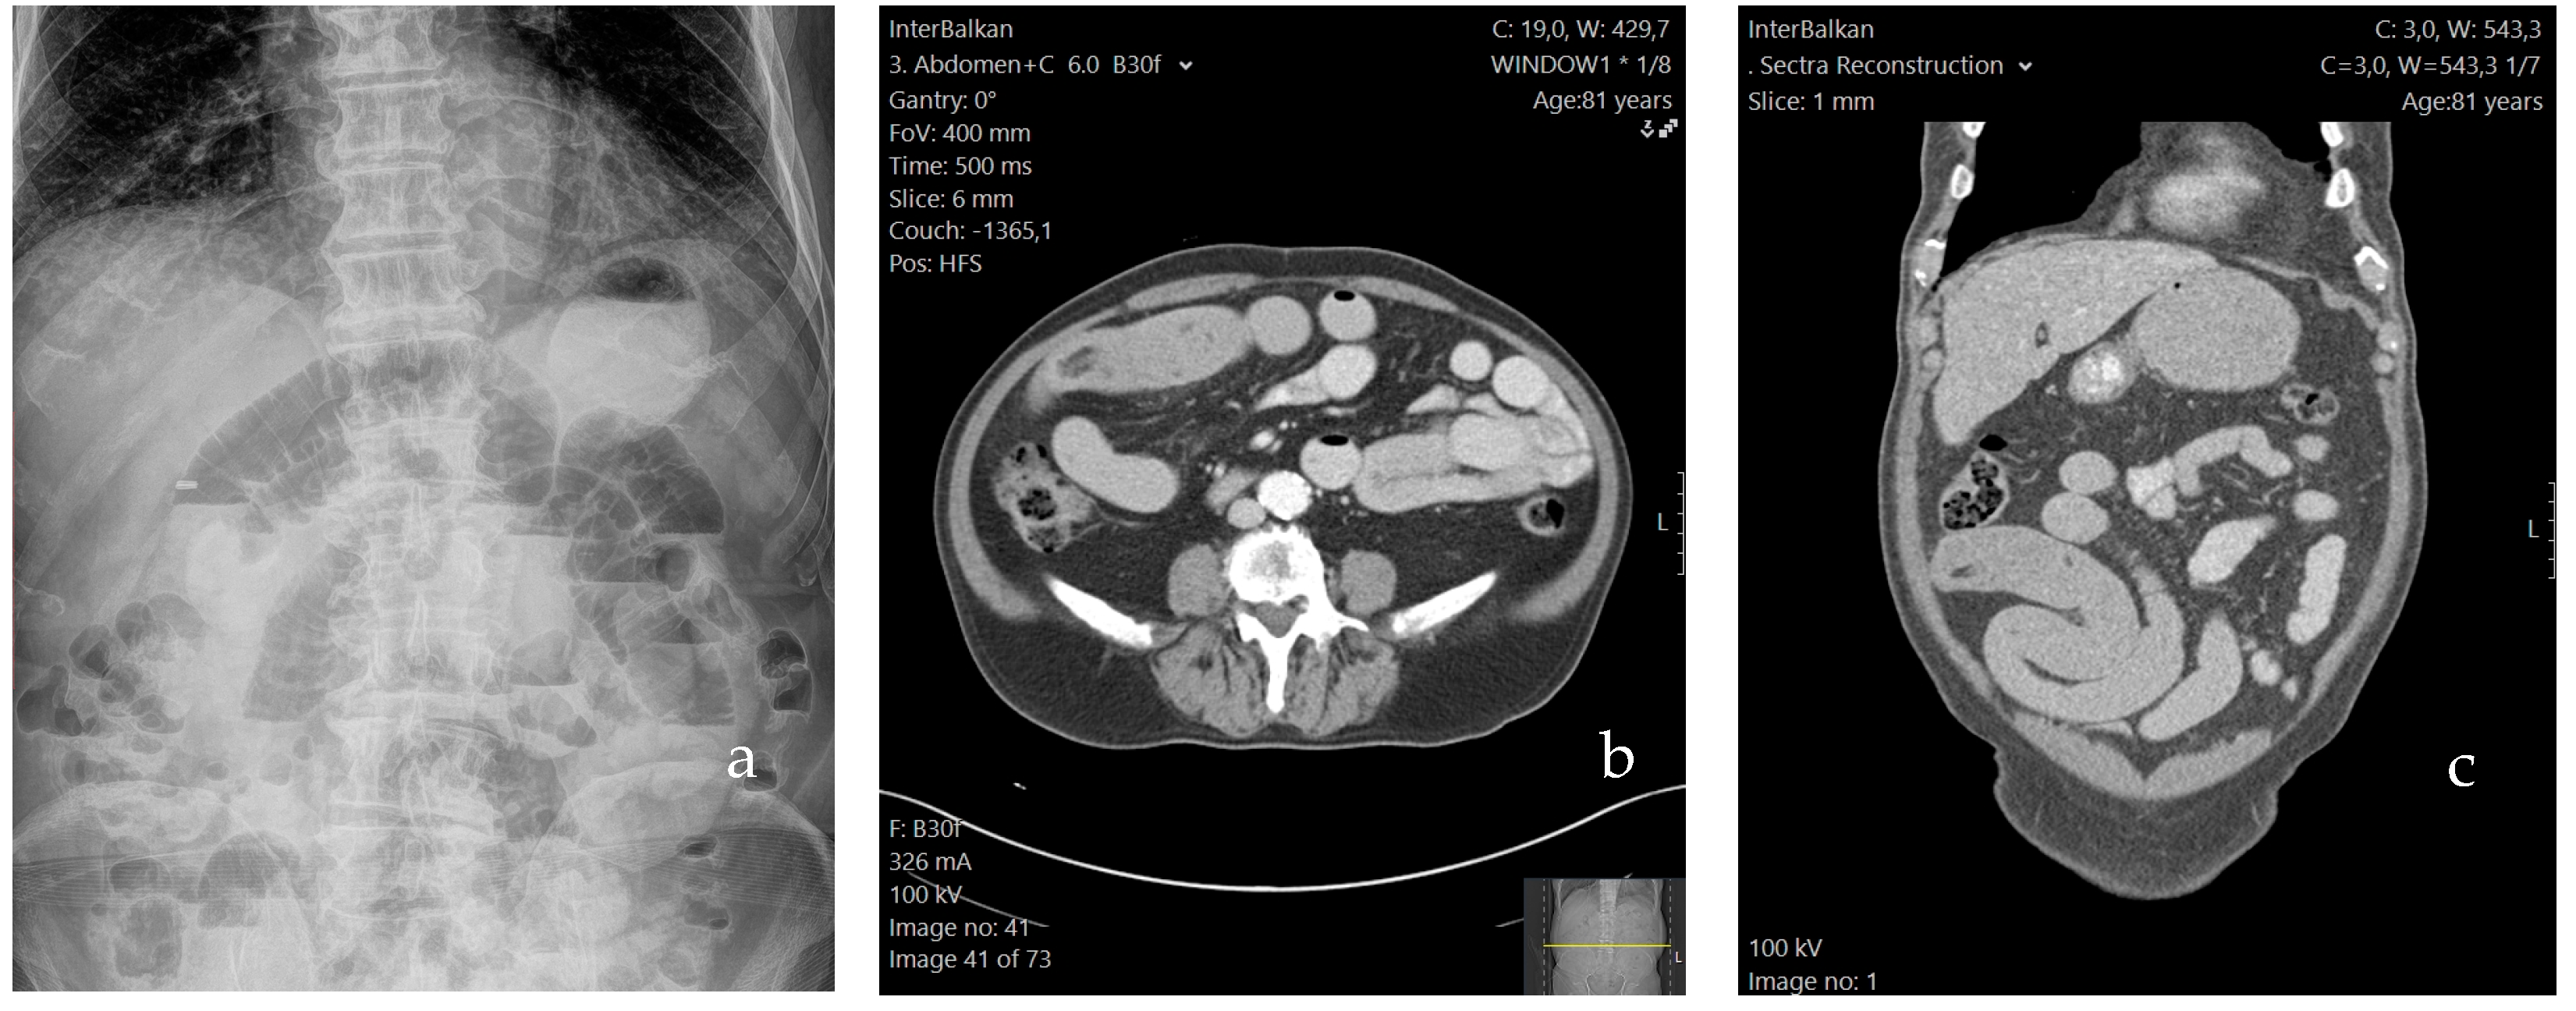

In the distended segment of the small bowel, visible ulcerations and hypertrophy of the mesenteric fat were also observed. Notably, the thickening and extension of the fat around the circumference of the intestine were similar to “creeping fat”, which is associated with Crohn’s disease (Figure 2a). Owing to the frailty of the intestinal wall and the ischemia resulting from the intussusception, we proceeded with segmental enterectomy 20 cm proximally to the ileocecal valve, with consequent entero-enteric side-to-side anastomosis, using linear surgical staplers. The entirety of the abdominal cavity was consequently rinsed with normal saline, and two drainage tubes were inserted bilaterally in the POD. The patient tolerated the procedure well.

An incision on the antimesenteric border of the surgical specimen revealed the presence of multiple bezoars. Additionally, at the sites of the bezoar’s lodging, the intraluminal wall exhibited prominent ulcerations and strictures (Figure 2b). The entirety of the surgical specimen was subsequently sent for histopathological examination, which disclosed the presence of three mucosal ulcers, which could have facilitated the bezoar’s formation. Inflammatory granulomatous tissue, with purulent cores, was observed peripherally. Plant cellular matter was identified in the extracted bezoars, thus setting the diagnosis of intestinal obstruction due to multiple phytobezoars.

Figure 2. Thickening and extension of the fat as seen intraoperatively, along with impending ischemia of the formerly intussuscepted segment of the small intestine (a). The surgical specimen; visible ulceration of the intraluminal wall and two phytobezoars, approximately 5 cm each (b).